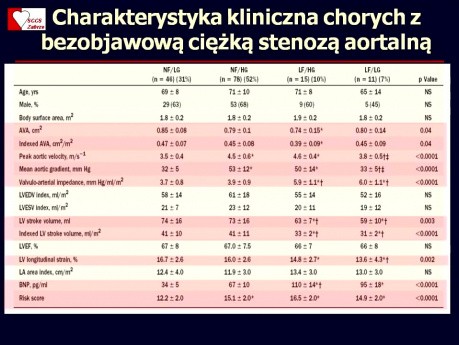

Bezobjawowa wada aortalna

Kiedy wymaga obserwacji a kiedy leczenia chirurgicznego? Wykład prowadzi dr hab. n. med. Tomasz Kukulski - kierownik pracowni Echokardiografii Dorosłych w Śląskim Centrum Chorób Serca w Zabrzu.